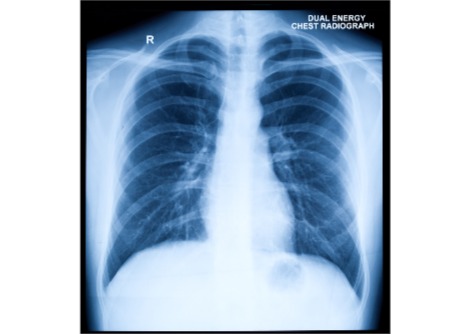

في غضون ذلك، ظلت مستويات بروتين يُسمى CRP مرتفعة. يقول ليز: "يتأثر CRP بعدد من العمليات المختلفة، ومن بينها الالتهاب بالتأكيد، ولكن عوامل مثل التغيرات الهرمونية يمكن أن تؤثر عليه أيضًا". في تحليل آخر، درس الفريق علامات لدى النساء المصابات بتسمم الحمل - وهي حالة أثناء الحمل يمكن أن يسبب فيها ارتفاع ضغط الدم الصداع ومشاكل في الرؤية والولادة المبكرة، ويؤدي إلى مضاعفات مميتة لكل من الأم والطفل إذا تُرك دون علاج. كشف هذا التحليل أن النساء المصابات بتسمم الحمل قبل الحمل لديهن مستويات مرتفعة من شظايا خلايا الدم التي تُسمى الصفائح الدموية وبروتين يُسمى ALT، مقارنةً بمن لم يُصبن بهذه الحالة.

يقول ليز: "لعقود، سادت فكرة أن المشيمة لا تُزرع بشكل صحيح، وإذا لم تُزرع بشكل صحيح، يُعطّل تدفق الدم، وتُطلق هرمونات ومواد تُسبب ارتفاع ضغط دم الأم". ويضيف: "لكن بعض الدراسات تُشير إلى أن وظائف القلب والأوعية الدموية لدى من يُصابون بها تختلف قبل الحمل - وهذه النتائج تُعزز هذه النظرية".

إذا أظهرت دراسات أخرى أن هذه العلامات قبل الحمل تُشير بالفعل إلى خطر الإصابة بتسمم الحمل، فقد تُستخدم لتحديد النساء الأكثر عُرضة للخطر. ويضيف ليز: "عندها يُمكن استهدافهن بطرق لتحسين صحتهن قبل الحمل - إما من خلال ممارسة الرياضة ونصائح نمط الحياة - لتقليل خطر الإصابة".